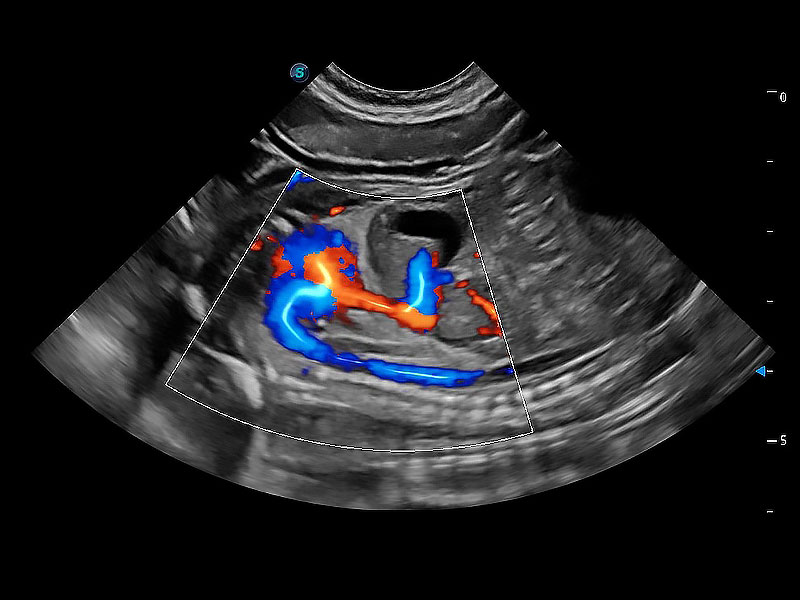

ProPet 80 配备了丰富的心脏探头群、先进的成像技术和专业的心脏测量工具,可帮助动物医生为不同体型和生理结构的动物提供心脏和心肌功能的全面评估。

实时用颜色表示心肌组织运动,观察和定量组织的运动情況,对快速检测与评估心肌的灌注和活性、电传导及心肌收缩和舒张功能等均能提供重要的诊断信息。

通过心肌识别技术与二维斑点追踪技术相结合,对心脏的超声图像进行量化分析。计算心肌17个节段的应变、应变率、速度、位移等,并通过牛眼图的形式进行呈现。

通过360度任意调节3条M型取样线,在同一心动周期上观察心脏不同位置的运动曲线,得到准确的心功能测量数据,有效评估心肌运动及左心室功能。